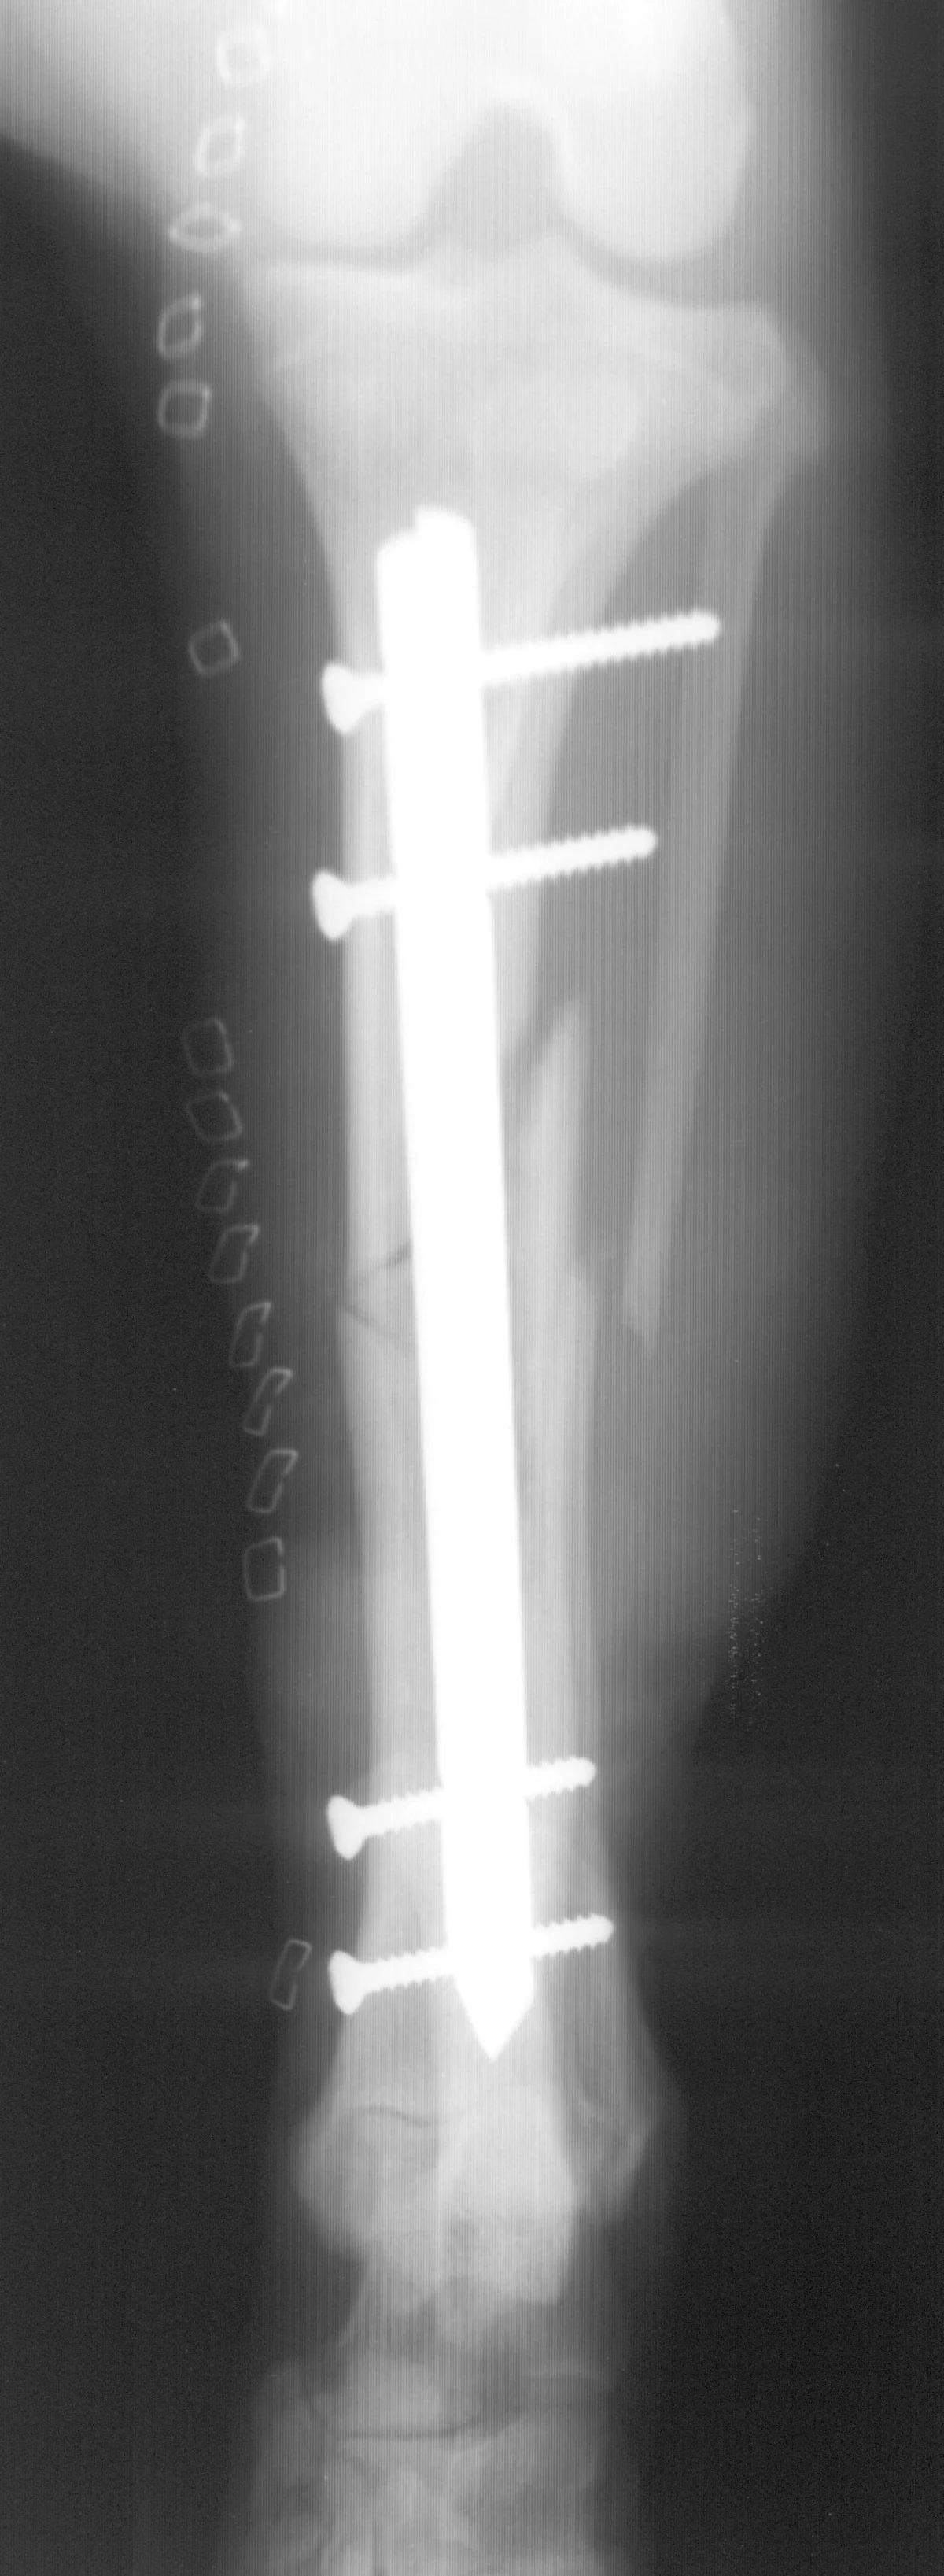

The combination of an IM pin and a bone plate has been found to be an ideal implant system for biologic management of comminuted fractures (Figure 1A) in dogs7 and cats. Adding an IM pin to the plate (Figures 1B, C) significantly increases stiffness and the estimated number of cycles to fatigue failure when compared with a plate-only system.

Adding an IM pin to a bone plate has been shown to reduce strain on the plate two-fold and subsequently increase the fatigue life of the plate-rod system 10-fold compared with the plate alone.2 In the canine femur, plate strain is reduced by approximately 19%, 44%, and 61% with the addition of an IM pin occupying 30%, 40%, and 50% of the marrow cavity, respectively.3

The IM pin is applied first. It can be used to assist distraction of the fracture as it engages the distal fragment. The pin provides axial alignment and provides partial stability for application of the plate.

The surgeon must be careful to attain rotational alignment before placing the screws of the bone plate. Only two to three screws are needed in the proximal and distal fragment. Monocortical screws are placed if the screw cannot be directed to avoid the IM pin. Open screw holes are protected by the IM pin and early bone callus, decreasing the chance of plate breakage.